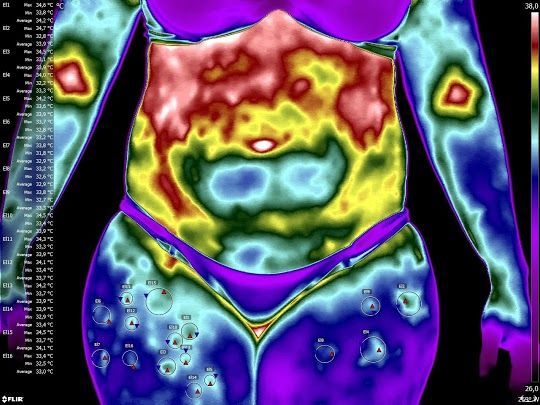

A termografia infravermelha é uma ferramenta funcional diagnóstica que mapeia a saúde do tecido através do calor. No seu consultório, ela atua da seguinte forma:

Detecção do Lipedema: Identifica a hipotermia relativa (áreas frias) causada pelo isolamento térmico da gordura doente e as "ilhas de calor" que indicam inflamação ativa (adiposite), diferenciando o lipedema da obesidade comum.

Cuidado (Monitoramento): Valida a eficácia de terapias como ozonioterapia e suplementação endovenosa. O sucesso é visualizado quando há uma homogeneização térmica, indicando melhora da microcirculação e redução da estase.

Pós-operatório de Plástica: Detecta precocemente complicações como seromas, hematomas ou infecções (hipertermia) antes de serem visíveis a olho nu, além de monitorar a evolução da fibrose e a recuperação do fluxo sanguíneo nos retalhos cutâneos.

Manejo da Dor Crônica: Localiza com precisão os pontos gatilho e disfunções neurovegetativas. Permite objetivar a dor da paciente, separando componentes inflamatórios de neuropáticos, o que direciona melhor o uso de fármacos.